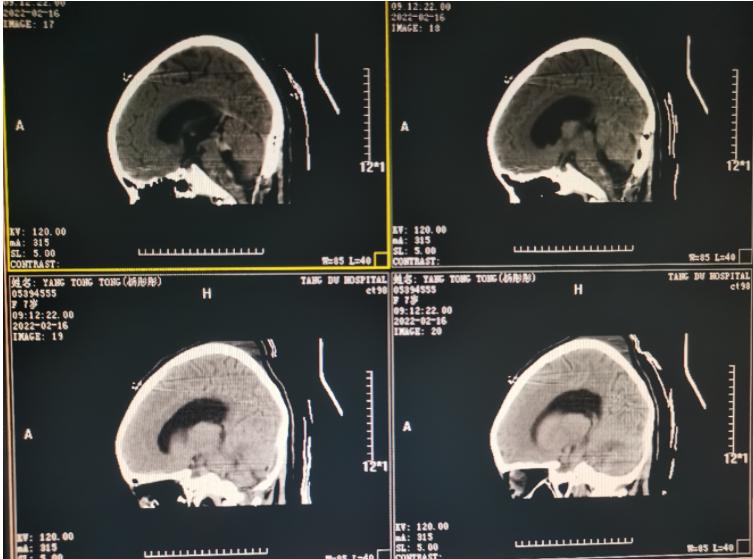

术后影像学资料:

手术做完后Amy的呕吐和头疼症状得到了明显地缓解,不久后孩子就回归了正常的学习生活,现在已经开心的坐在教室上课了。